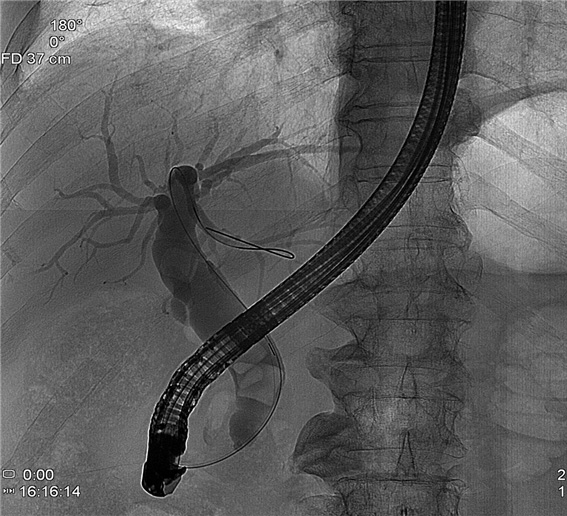

증례 1. 복통으로 내원하여 담도 결석에 의한 담도염 진단 환자에서 담도내시경을 이용한 담도 결석 제거술 시행 1예